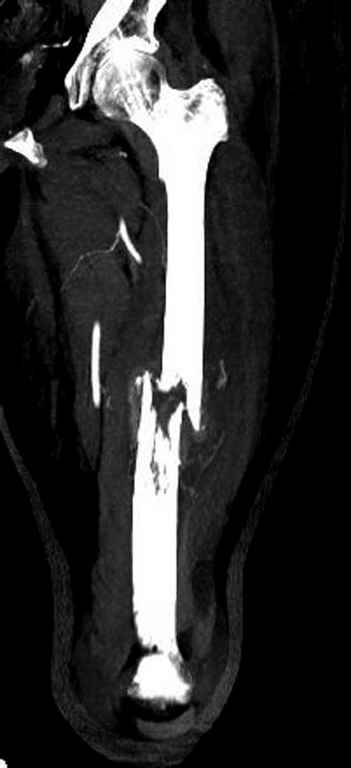

С минимальным рассверливанием и ретроградным методом провели остеосинтез бедра 12 мм гвоздем. (17-20)

Кровопотеря во время операции меньше 100 мл.

Больная выписана, взятый во время рассверливания материал изучается.